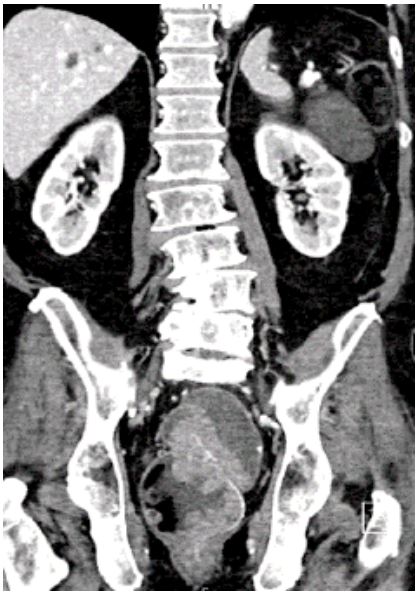

Abdominal X-ray showed dilated bowel loops suggestive of sigmoid volvulus. This prompted a call for CT abdomen to identify any evidence of obstruction and possible third space electrolyte depletion. Subsequent CT Abdomen and pelvis- Figure 1 showed a large villous recto sigmoid polypoid lesion which measured 68 mm x 43 mm (AP x ML).

Figure 1: Large villous recto sigmoid polypoid lesion.